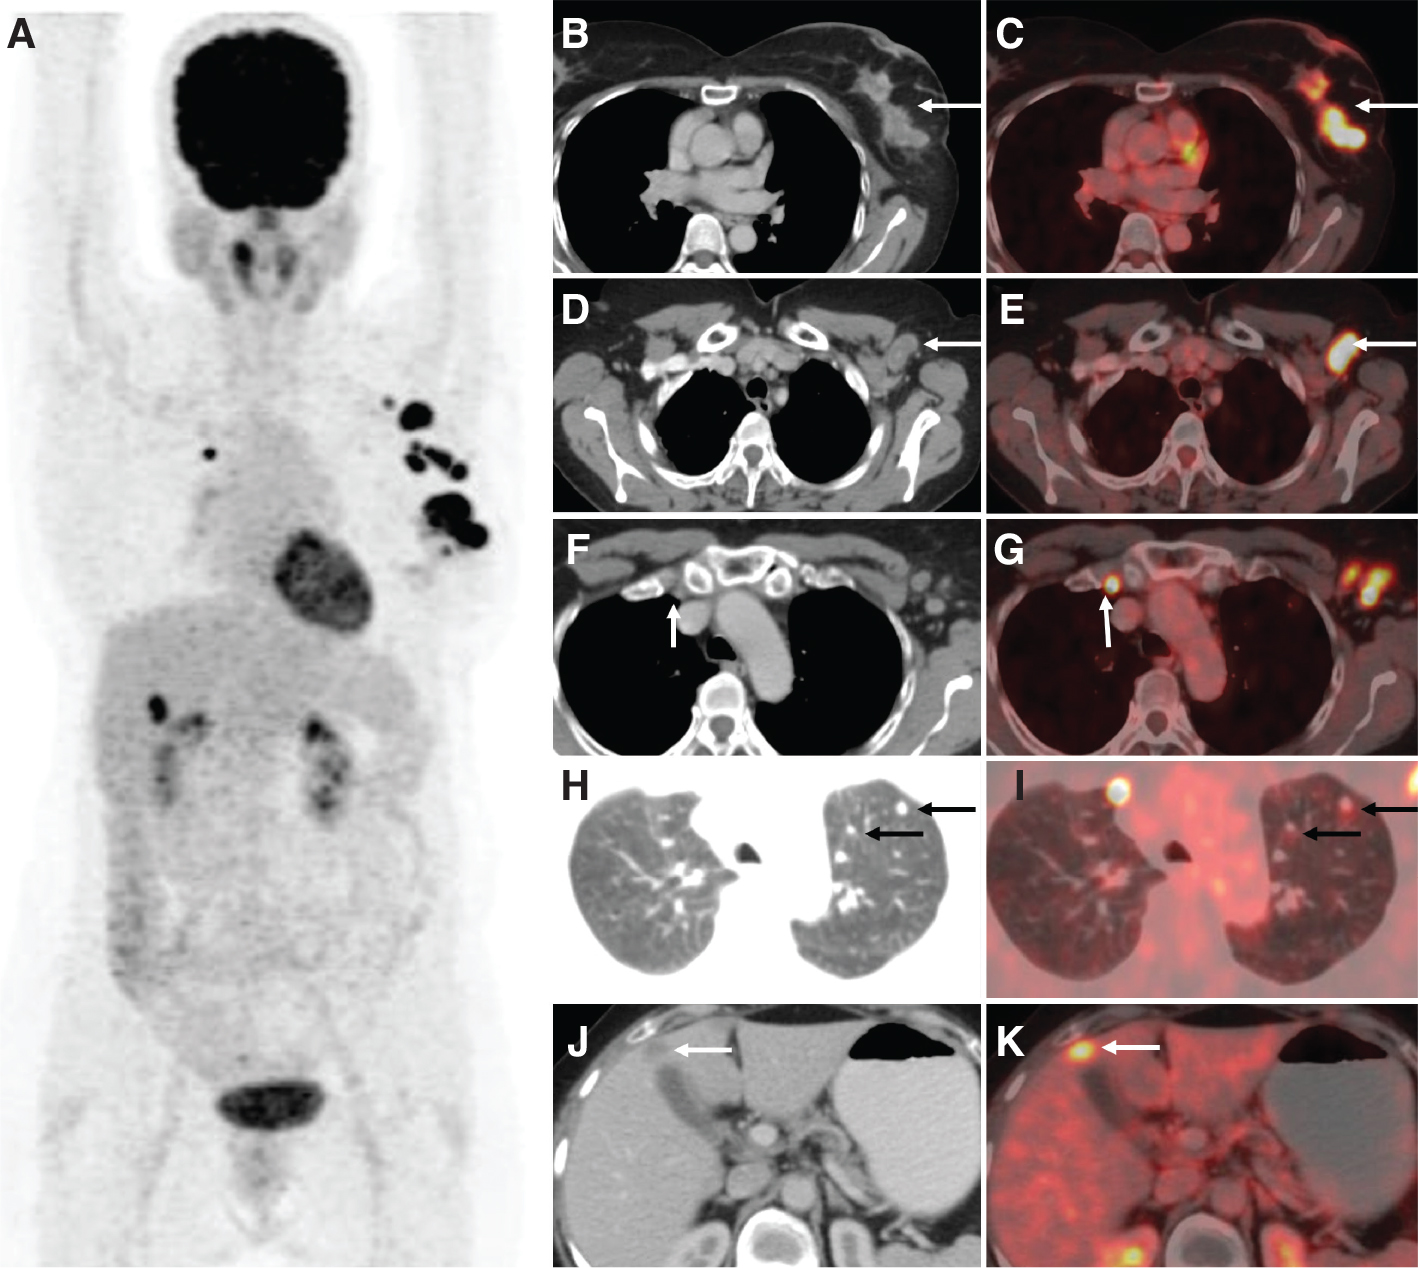

Fig 1

Figure 1. 18F-FDG PET/CT in carcinoma breast. A female with lump in the left breast, which was proven to be infiltrating ductal carcinoma on histopathology. Clinical stage was T2N1Mx with palpable axillary lymph nodes. 18F-FDG PET/CT was performed for staging the disease as part of pre-operative workup, which showed multiple foci of increased FDG uptake in the chest and upper abdominal region on the MIP image (A). The trans-axial CECT and fused PET/CT images showed a FDG avid heterogeneously enhancing lesion in the upper outer quadrant of left breast with multiple satellite nodules (B, C), FDG avid enlarged left level I axillary lymph nodes (D, E), a FDG avid sub centimeter right internal mammary lymph node (F, G), lung nodules (H, I) and a FDG avid hypodense lesion in the liver (J, K). The final stage post PET/CT was T3N1M1, which led to a change in management from surgery to systemic chemotherapy as patient’s classification was changed from having an operable breast cancer to an inoperable breast cancer with metastatic disease.